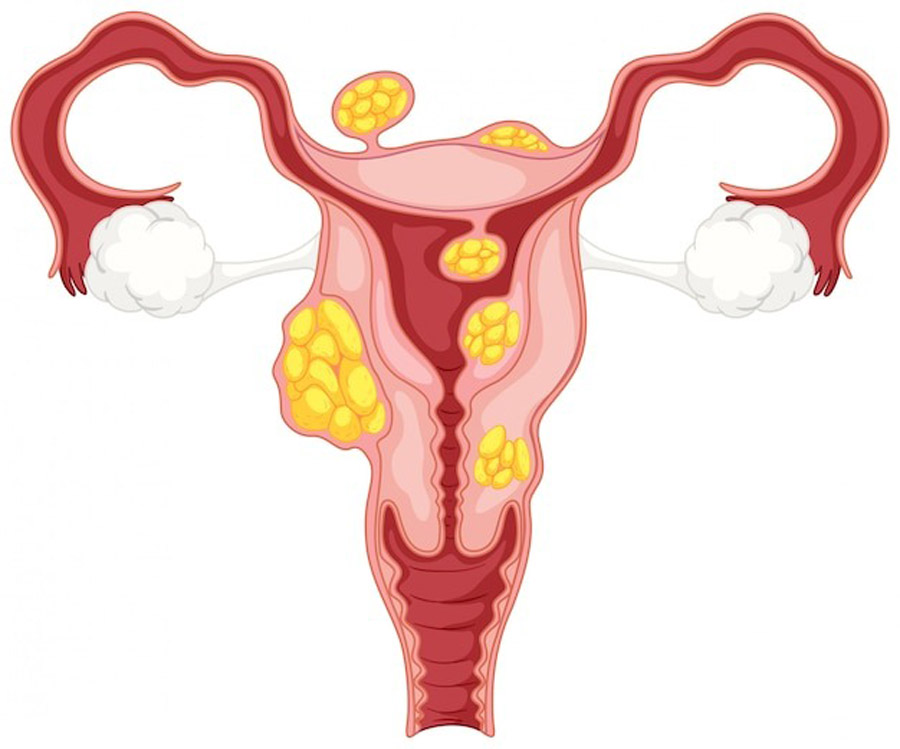

قیمت: 45٬000 تومان - دسته بندی فایل: پاورپوینتدانلود پاورپوینت آشنایی با کیست آندومتریوما

خرید پاورپوینت حرفه ای با موضوع آشنایی با کیست آندومتریوما با قیمت استثنایی از لوکس فایل